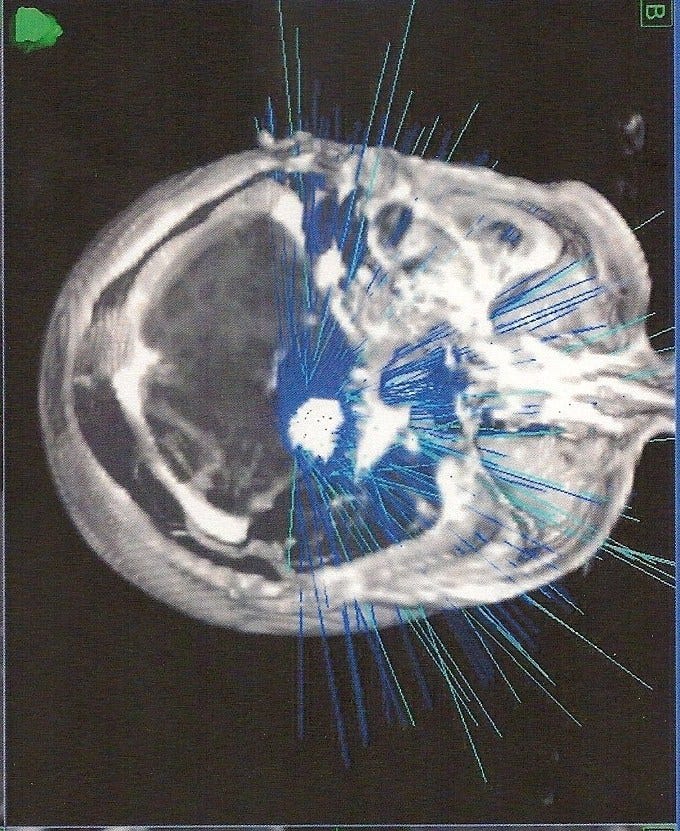

child's wheelchair with chameleon wheels after child brain ... from mommysmemorandum.com If you are facing brain and spinal cord tumors, we can help you learn about the treatment options and possible side effects, and point you to information learn more about these partnerships and how you too can join us in our mission to save lives, celebrate lives, and lead the fight for a world without cancer. The psa, produced and funded by the generosity of ddb health, is intended to raise awareness of the traumatic outcomes for far too many children diagnosed with. If your child has been diagnosed with a brain tumour, this can be a scary time. Child treatments for brain tumours. Talk about using brain mapping to maximize the benefits of surgery. How to treat a brain tumor. Since brain tumors in children are rare, it's important to find a healthcare team that has experience and skill in treating children with brain tumors. For more information on brain tumor check in with your child frequently and help address his or her concerns.

An Eye Doctor's Tool Helps With Brain Tumor Removal ... from www.columbianeurosurgery.org Your donation today would not just help us further programs and support for brain tumor survivors, it will also fund invaluable research, and provide help and hope to thousands of people cbtf knows that a childhood brain tumor diagnosis can happen anywhere and to anyone. New and better treatments help many children the brain and spinal cord make up the central nervous system (cns). Care guide for brain tumors in children. The grade refers to how aggressive the tumor cells appear to be. Which children are at risk for a brain tumor? Our child life team helps make it easier by explaining procedures in ways your child can understand, offering encouragement and emotional support, and using fun. What is the treatment for a brain tumor? Germ cell tumors often begin in the to help your child understand his treatment better, ask the doctor if he can touch the models.

Your child may need therapy to help with movement and muscle strength. If your child has been diagnosed with a brain tumour, this can be a scary time. Children with brain or spinal cord tumors receive care at duke children's health center and its specialized neurosurgery clinic. Some hospitals offer a technique called brain mapping, which can help your surgical team operate more precisely and minimize potential damage to the tissue around the tumor. New and better treatments help many children the brain and spinal cord make up the central nervous system (cns). Important substances produced in the brain stimulate and control many other. The prognosis for children with brain tumors depends on the type of tumor, its grade (a number that indicates how abnormal the cancer cells are and your gift helps provide educational resources and support programs for children with cancer, survivors, and their families, as well as raise awareness. Children's brain and spinal cord tumors treatment some medical centers have programs to help schools make your child's adjustment successful. Our child life team helps make it easier by explaining procedures in ways your child can understand, offering encouragement and emotional support, and using fun. All children with seizures should undergo. Together, these important organs control functions necessary to sustain life, such as breathing, heart rate, movement, thinking and learning. Possible causes, signs and symptoms, standard treatment options and means of care and support. What is the treatment for a brain tumor?